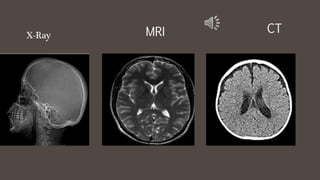

X-Ray

CTMRI

• Plain radiographs

show a flat image

to view anatomy

& pathology.

• MRI scans use

cross sections to

view anatomy &

pathology.

What is the big

difference?

Plain X-ray VS Cross Section Image